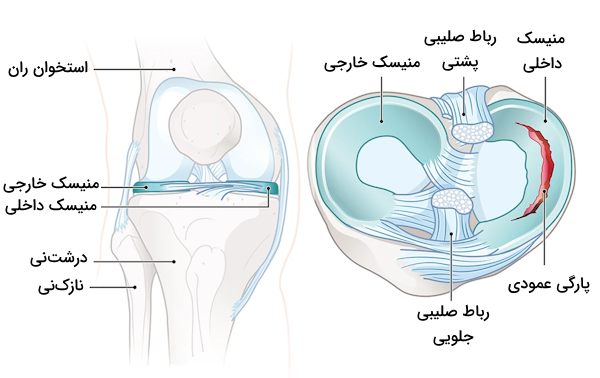

به طور معمول سطوح مفصلی موجود در مفصل تیبیوفمورال نامتجانس یا ناهمجور هستند، به همین دلیل برای آن که تطابق بهتری ایجاد شود، شاهد حضور منیسکهای داخلی و خارجی هستیم. منیسکها ساختارهایی «فیبروغضروفی» (Fibrocartilaginous) هستند که ظاهری هلالیشکل دارند و وظیفه آنها توزیع یکنواخت فشار فمور روی تیبیا (درشتنی) است.

منیسکهای زانو

منیسکهای زانو صفحاتی هلالی شکل از جنس «فیبروکارتلاژین» (Fibrocartilaginous) هستند که در سطوح مفصلی فمور و تیبیا (استخوان ران و درشتنی) وجود دارند. منیسکها دو نقش بسیار مهم برعهده دارند.

- ایجاد تطابق یا همنهشتی بین دو سطح مفصلی: این عمل باعث افزایش ثبات و پایداری مفصل زانو میشود.

- ضربهگیری: منیسکها با افزایش ناحیه سطح تماس، نیروهایی که از طریق مفصل منتقل میشوند را پخش میکند و به این ترتیب فشار وارد شده کاهش مییابد.

در زانو دو منیسک داخلی و خارجی وجود دارد که هر دو آنها به انتهای ناحیه بین کوندیلی استخوان درشت نی متصل هستند. منیسک داخلی اتصالات دیگری نیز دارد که به شرح زیر هستند.

- اتصال به «رباط طرفی خارجی» (Medial Collateral Ligament)

- اتصال به کپسول مفصل

بنابراین اتصال بین منیسک داخلی و رباط طرفی خارجی، دلیل پارگی منیسک داخلی پس از وارد شدن آسیب به رباط طرفی خارجی است. منیسک خارجی که کوچکتر از منیسک داخلی است، به دلیل نداشتن هیچ اتصال اضافی، تحرک بیشتری دارد. به طور کلی باید گفت که حفظ موقعیت منیسکها و نگهداری آنها بر عهده چندین رباط است که در ادامه با آنها آشنا میشویم.

منیسک داخلی زانو

«منیسک داخلی» (Medial Meniscus) صفحهای فیبروغضروفی با ظاهری هلالی (مشابه با حرف C انگلیسی) و نیمدایرهای است که روی سطح صفحه تیبیای داخلی قرار گرفته است. شاخ جلویی منیسک داخلی به ناحیه بین کوندیلی جلویی درشتنی متصل است و به رباط صلیبی جلویی میپیوندد. شاخ پشتی نیز به ناحیه بین کوندیلی پشتی درشتنی، بین اتصالات منیسک خارجی و رباط صلیبی پشتی، متصل است.

منیسک خارجی زانو

«منیسک خارجی» (Lateral Meniscus) صفحهای فیبروغضروفی و به نسبت دایرهای است که سطح صفحه تیبیای خارجی را میپوشاند. شاخ جلویی این منیسک نیز، مشابه با منیسک داخلی، به ناحیه بین کوندیلی جلویی درشتنی متصل است، اما منیسک خارجی به طور کامل به رباط صلیبی جلویی نمیپیوندد و تا حدی با آن ترکیب میشود. ناحیه پشتی منیسک خارجی به ناحیه بین کوندیلی پشتی در بخش جلویی شاخ پشتی منیسک داخلی متصل است.

پارگی منیسک

منیسکها ساختاری محکم و انعطافپذیر دارند که همین موضوع باعث میشود بتوانند به عنوان ضربهگیر بین استخوانهای ران و درشتنی فعالیت کنند، اما منیسکها میتوانند در شرایطی به خصوص پاره شوند، برای مثال در صورتی که زانوی خود را در حالی که زیر فشار وزن بدن است، خم کنید، ممکن است منیسک دچار پارگی شود.

پارگی منیسک توسط بسیاری از افراد، به خصوص اشخاصی که بیش از ۵۰ سال دارند، تجربه میشود. به طور معمول در صورتی که علت پارگی منیسک بالا رفتن سن باشد، جراحی توصیه نمیشود اما با توجه به شرایط هر فرد متخصصان تصمیمات مناسبی را اتخاذ میکنند که میتوانند شامل جراحی منیسکها نیز باشند.